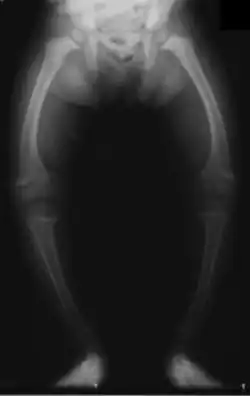

Rickets

Rickets, a childhood disease, is characterized by impeded growth and soft, weak, deformed long bones that bend and bow under their weight as children start to walk. Maternal vitamin D deficiency can cause fetal bone defects from before birth and impairment of bone quality after birth.[81][82] Rickets typically appear between 3 and 18 months of age.[83] This condition can be caused by vitamin D, calcium or phosphorus deficiency.[84] Vitamin D deficiency remains the main cause of rickets among young infants in most countries because breast milk is low in vitamin D, and darker skin, social customs, and climatic conditions can contribute to inadequate sun exposure. A post-weaning Western omnivore diet characterized by high intakes of meat, fish, eggs and vitamin D fortified milk is protective, whereas low intakes of those foods and high cereal/grain intake contribute to risk.[85][86][87] For young children with rickets, supplementation with vitamin D plus calcium was superior to the vitamin alone for bone healing.[88][89]